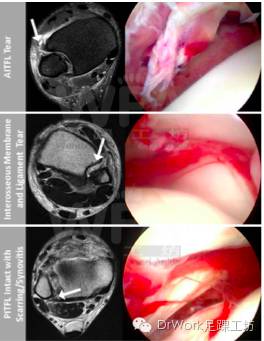

3.关节镜评估

• 较之术前平片和MRI检查、应力试验,关节镜可以更直观提供AITFL和PITFL损伤依据

• 关节镜可同时明确诊断和处理踝关节游离体、距骨骨软骨损伤